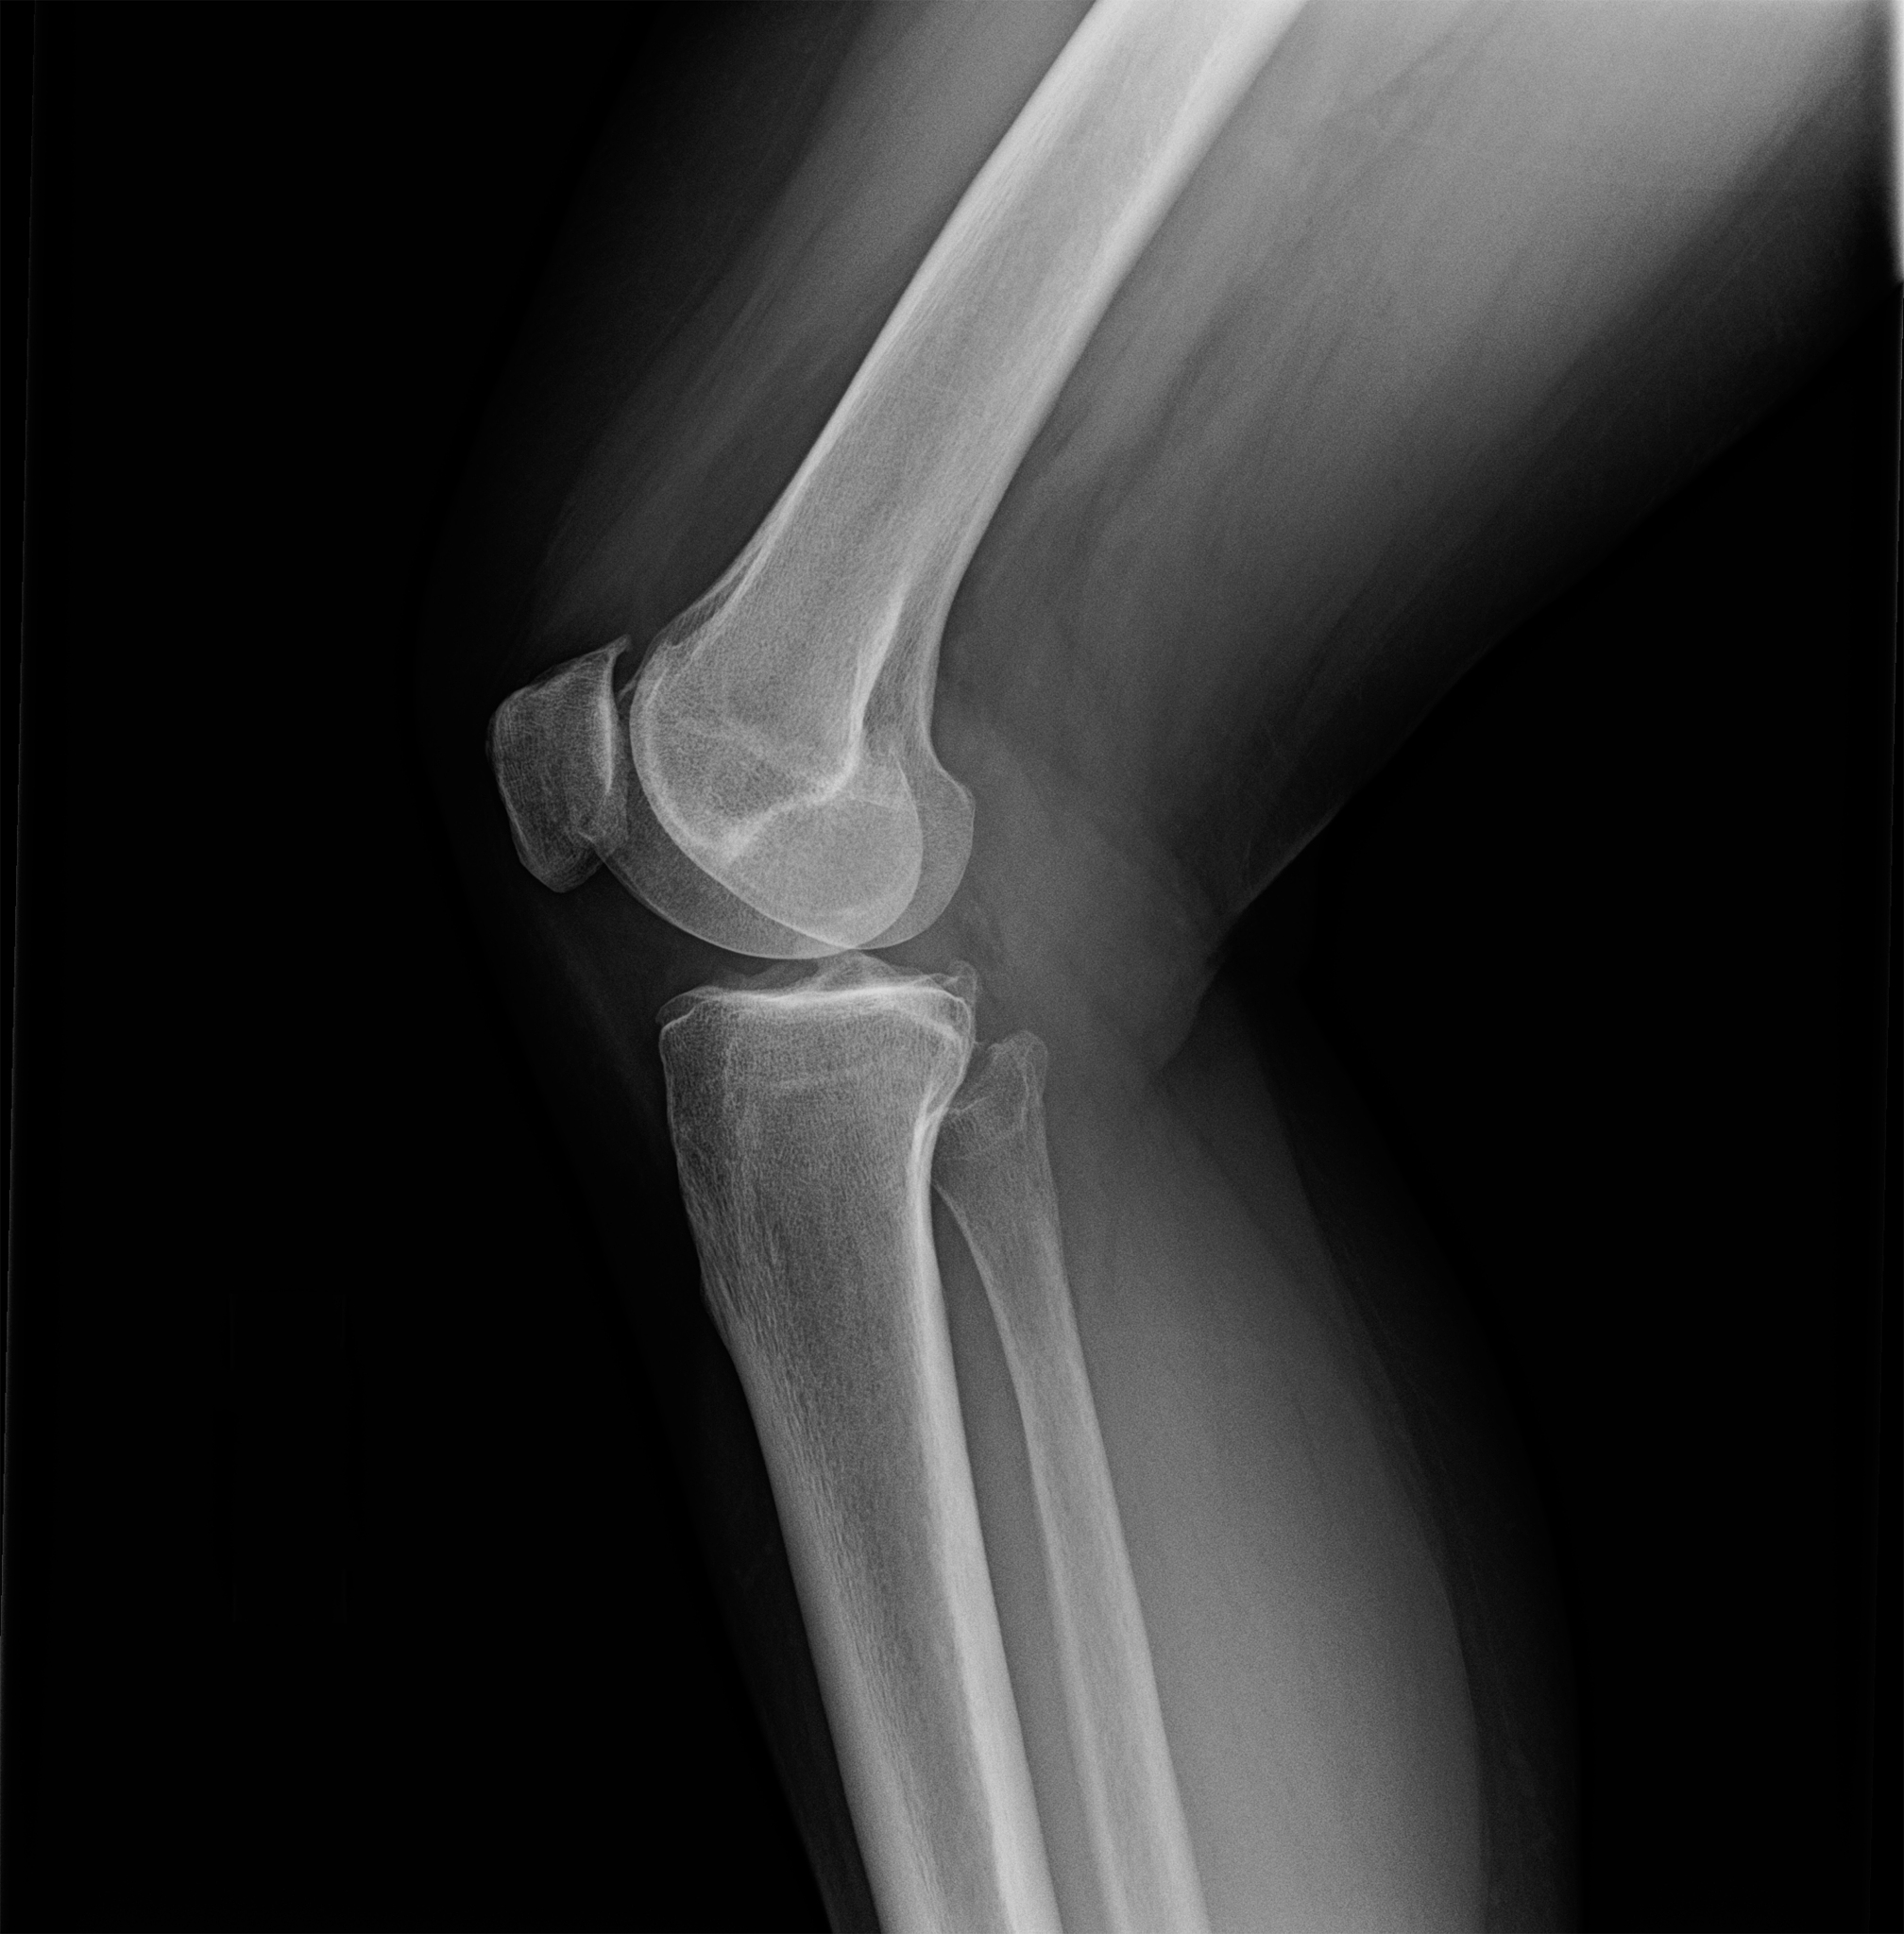

腓骨头上入路是一种治疗伴有后外侧塌陷的胫骨平台骨折的有效手术方法。该手术方式通过腓骨头上的切口进入骨折部位,从而实现骨折复位和固定。

1. **麻醉:**患者通常需要接受全身麻醉,以确保手术过程中的舒适度和安全性。2. **入路:**医生会在腓骨头上方选择合适的入路点,通常位于胫骨平台的后外侧。3. **骨折复位:**医生通过入路点进入骨折部位,将骨折的碎骨片复位到正确的位置。4. **内固定:**医生使用金属板和螺钉固定骨折部位。金属板和螺钉的选择和放置方式取决于患者的具体情况。5. **术后检查:**完成固定后,医生会进行X射线检查,以确保骨折部位得到正确复位和固定。6. **术后康复:**术后,患者需要进行康复训练和物理治疗,以促进骨折愈合和功能恢复。